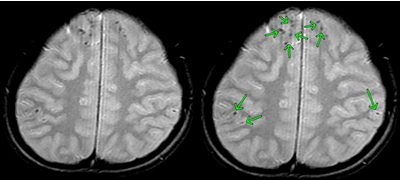

びまん性軸索損傷の具体例

症状固定段階でのT2スター強調のMRI画像です。頭頂部から頭蓋底に至る24枚のMRI画像の内の6枚目の画像です。

前頭葉、両側頭葉に黒い点がいくつか映っています。これは、脳表面の広範囲に広がる点状出血が画像として映ったものです。びまん性軸索損傷があることを示します。

点状出血を矢印で示したものが下の画像です。

被害者はフルフェイスのヘルメットを装用していました。頭蓋骨骨折や脳挫傷はありませんでした。

しかし、広範囲の点状出血に伴う軸索の損傷があります。失語、記憶、聴覚や嗅覚、言語理解、認知の領域で、脳は大部分の機能を喪失してしまいました。